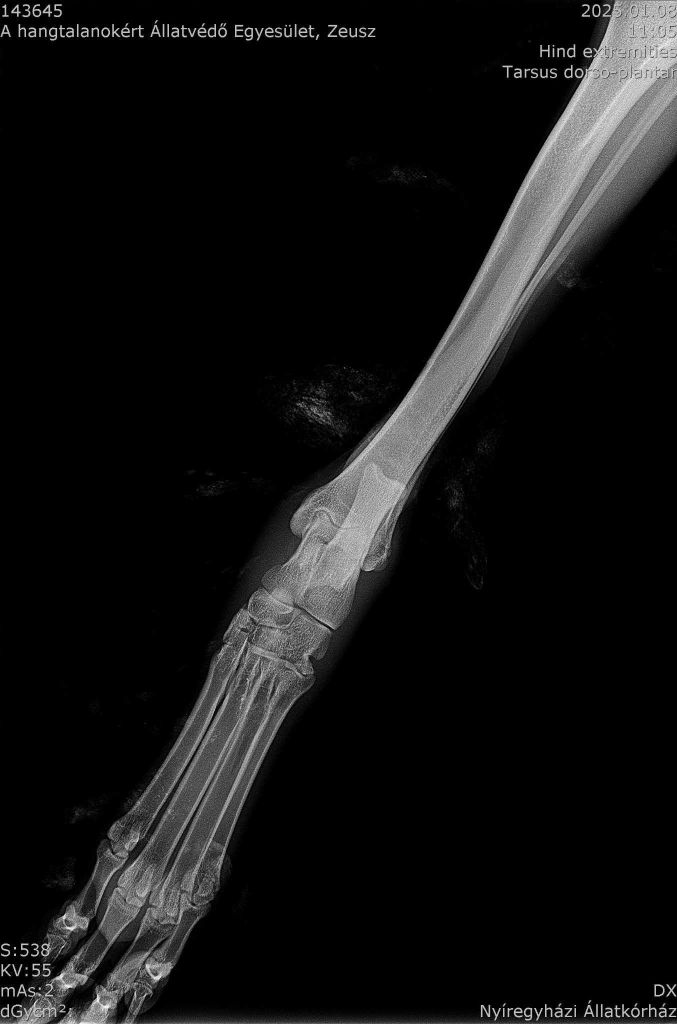

Das Röntgenbild hat verdeutlicht, dass Zeus nicht nur einen Bänderriss hat. Er hat ebenso eine Luxation im Fußgelenk. Das bedeutet seine Knochen haben ihre natürliche Ausrichtung verändert, wodurch Zeus Schmerzen im Sprunggelenk hat und nicht richtig laufen kann. Zeus wird daher diese Woche operiert, damit er bald wieder schmerzfrei laufen kann.